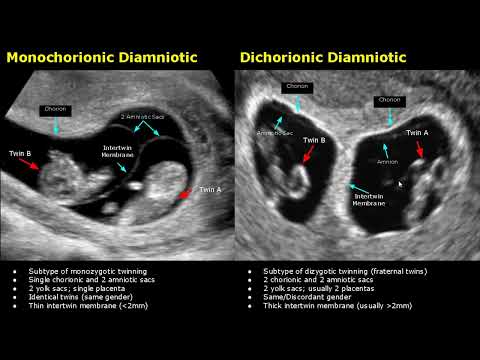

др.Кристинка Пајаковска гостуваше во емисијата Фактор Здравје на телевизија Алфа. Тема: Прегледи во бременост Повеќе информации на телефоните: +389 47 208 880 +389 47 208 881 www.plodnost.com.mk